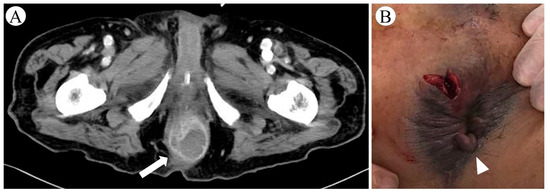

2. Case Presentation